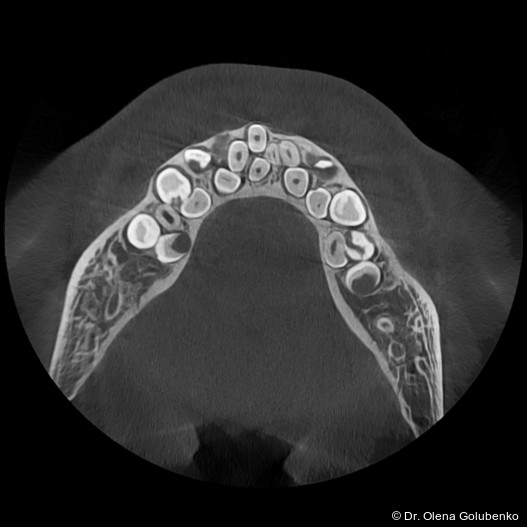

Die dreidimensionale Bildgebung zeigt meist eine hohe Anzahl nicht durchgebrochener permanenter und überzähliger Zähne, die in unterschiedlicher Lage im Kiefer verbleiben (Abb. 3+4).

Die Diagnostik der cleidokranialen Dysplasie basiert auf einer sorgfältigen klinischen Untersuchung, der Analyse von Panoramaaufnahmen sowie insbesondere auf der digitalen Volumentomografie (DVT). Ziel ist es, die Anzahl, Lage, den Entwicklungsstand sowie mög­liche Interferenzen der retinierten und überzähligen Zähne präzise zu erfassen und in ei­nen funktionellen sowie skelettalen Kontext einzuordnen (Abb. 5–8).